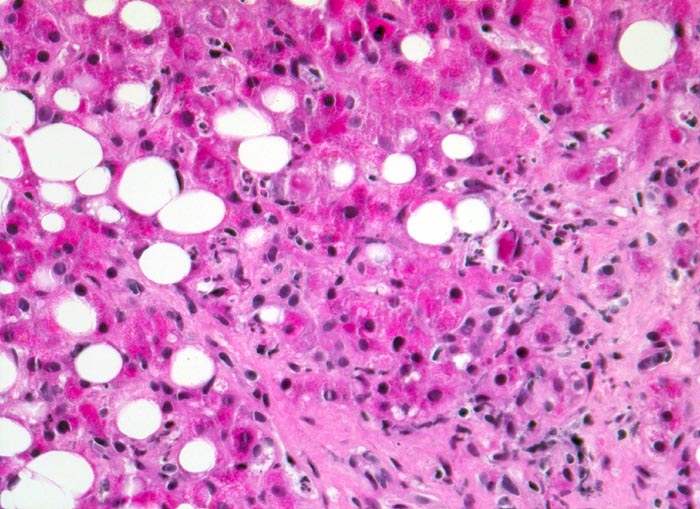

PathoPic ID 4948 - hochfloride chronische sklerosierende alkoholische Steatohepatitis

hochfloride chronische sklerosierende alkoholische Steatohepatitis

Grobtropfige Parenchymverfettung. Zahlreiche

neutrophile Granulozyten infiltrieren das Parenchym.

Alkoholabusus

Histologie

200